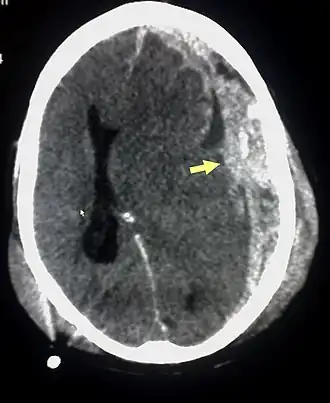

Sur le scanner crânien, fait sans injection de produit de contraste, l'hématome sous-dural se présente habituellement sous une forme de croissant, dont la concavité suit la courbe du cerveau, stoppé seulement par les réflexions durales telles que la faux du cerveau et le tentorium. Cependant ils peuvent avoir une forme convexe, spécialement tout au début du saignement, ce qui peut les faire confondre avec les hémorragies épidurales (hématome extradural). Le sang peut être vu comme une densité stratifiée tout au long du tentorium. Dans les cas chroniques, on peut voir l'effacement des sillons ou le déplacement médian de la jonction substance blanche/substance grise, mais le sang peut avoir une densité très proche de celle du tissu cérébral (isodense), ce qui peut masquer l'hématome.

Les hématomes sous-duraux sont plus fréquents dans les parties supérieure et latérales du frontal et au niveau des lobes pariétaux[5],[12] ainsi que dans la fosse postérieure proche de la faux du cerveau et de la tente du cervelet[5].